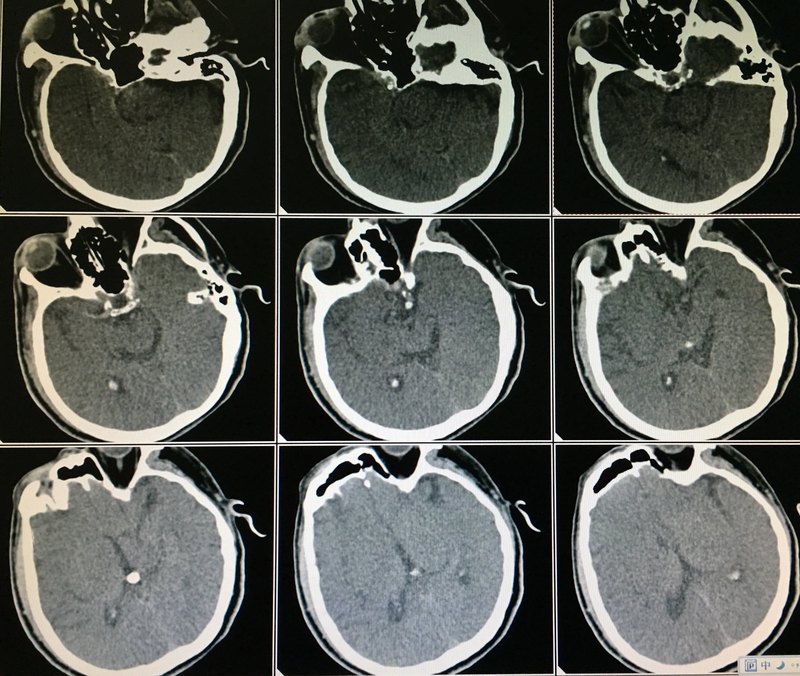

腦出血、腦血栓、腦栓塞的區(qū)別介紹這三者的區(qū)別核心提示:腦出血、腦血栓、腦栓塞是三種比較常見的腦部疾病。它們之間僅一字之差。很多朋友都分不清什么是腦出血,什么是腦血栓以及腦栓塞。因為這三種疾病都會使患者出現(xiàn)頭疼,嘔吐等臨床癥狀。其實這三種疾病是有很大區(qū)別的。心腦血管是目前對我們的生命健康構(gòu)成威脅最大的一類疾病。心腦血管疾病病情復雜,種類繁多。因此對于我們來說區(qū)分它們是非常復雜的。腦出血、腦血栓、腦栓塞這三種常見的心腦血管疾病只有一字之差,因此區(qū)分它們似乎變得很困難。下面針對腦出血、腦血栓、腦栓塞的區(qū)別做個簡單的介紹。腦出血發(fā)生的原因與腦血管的病變有關(guān)。常見的致病原因包括高血脂、糖尿病、高血壓、血管的老化、吸煙等。腦出血患者最主要的癥狀為劇烈頭痛和嘔吐。患者在腦出血后,血壓會出現(xiàn)明顯的升高。腦出血比較嚴重的患者會出現(xiàn)意識模糊或昏迷,有的患者會由于出血而立即死亡。腦血栓是由于腦血管自身的狹窄或閉塞,導致腦組織缺血、軟化、壞死而產(chǎn)生的。腦血栓形成多發(fā)生于中老年患者。它起病緩慢,常于數(shù)十小時或數(shù)日內(nèi)病情達到高峰。一般在發(fā)病前有先兆癥狀?;颊邥霈F(xiàn)半身不遂,語言不利,頭痛、嘔吐等癥狀。腦栓塞是由于腦血管被血流中所帶來的固體、氣體、液體等栓子阻塞而引起的。腦栓塞主要的患者人群為青壯年,起病急驟,一般幾分鐘癥狀便全部出現(xiàn),且發(fā)病前無前軀癥狀。腦栓塞患者常見的臨床表現(xiàn)有偏癱、口角歪斜、流口水、不能說話或者言語不清,肢體功能障礙,手腳麻木等癥狀。以上就是腦出血、腦血栓、腦栓塞這三種心腦血管疾病的區(qū)別。由于這三種疾病的致病原因不同,因此它們的治療方法也是有一定的區(qū)別的。如果出現(xiàn)心腦血管疾病,應(yīng)該及時去醫(yī)院做一個詳細的腦CT檢查。待確定所患疾病之后再進行及時的根治。轉(zhuǎn)自http://tag.120ask.com/jibing/naochuxue/842041.html

心源性卒中是心源性栓子導致的心源性腦栓塞,可致流域性梗死和分水嶺梗死,心源性栓子不僅致心源性卒中(含小卒中),也可致短暫性腦缺血發(fā)作(TIA)。引起腦栓塞常見的心臟疾病有心房顫動、心瓣膜病、感染性心內(nèi)膜炎、心肌梗死、心肌病、心臟手術(shù)、先天性心臟病等。其中,心房顫動是引起心源性腦栓塞最常見的原因。腦栓塞可發(fā)生于腦的任何部位,因左側(cè)頸總動脈直接起源于主動脈弓,故發(fā)病部位以左側(cè)大腦中動脈的供血區(qū)較多,其上干是最常見的發(fā)病部位。因起病迅速,無足夠時間建立側(cè)枝循環(huán),所以栓塞與發(fā)生在同一動脈的血栓形成相比,病變范圍大。腦栓塞引起的腦部缺血性壞死,出血性更為常見,占30——50%。最初栓塞動脈的血管壁已受損,血流恢復后易從破損的血管壁流出,形成出血性梗死。臨床中任何年齡均可發(fā)病,患者多有風濕性心臟病或心房顫動。一般無發(fā)病誘因,也少有前驅(qū)癥狀。腦栓塞是起病速度最快的一類腦卒中,癥狀常在數(shù)秒或數(shù)分鐘達到高峰,多為完全性卒中。偶爾病情在數(shù)小時內(nèi)進展,癥狀加重。起病后多數(shù)患者有意識障礙,但持續(xù)時間較短。當顱內(nèi)大動脈或椎—基底動脈栓塞時,腦水腫導致顱內(nèi)壓升高,短時間內(nèi)患者出現(xiàn)昏迷。腦栓塞造成急性腦血液循環(huán)障礙,引起癲癇發(fā)作,其發(fā)生率高于腦血栓形成。發(fā)生于頸內(nèi)動脈系統(tǒng)的腦栓塞約占80%,而發(fā)生于椎—基底動脈系統(tǒng)的約占20%。臨床癥狀取決于栓塞的血管及栓塞位置。約30%的腦栓塞為出血性梗死,可出現(xiàn)意識障礙突然加重或肢體癱瘓加重。輔助檢查可用頭部CT及MRI,顯示栓塞部位和范圍。還應(yīng)常規(guī)進行心電圖、胸部X線片和超聲心動圖檢查。特殊檢查還包括24小時動態(tài)心電圖監(jiān)護、經(jīng)食管超聲心動圖等。頸動脈超聲、頸部血管MRA和DSA檢查對評價顱內(nèi)外動脈的狹窄程度和動脈斑塊有意義。心源性栓塞診斷要點:大面積或急性多發(fā)梗死灶,高危心源性栓塞證據(jù)。增加新發(fā)房顫檢出辦法包括連續(xù)多次的心電圖檢查、Holter和延長心電監(jiān)測時間,超聲心電圖附壁血栓不是必要條件,排除動脈粥樣硬化性狹窄或其他能引起多發(fā)梗死的病變,進行腦動脈影像學檢查。

腦動脈急性栓塞的血管內(nèi)取栓治療

腦動脈急性閉塞可導致的病人死亡,存活的病人也有偏癱、失語、偏盲等嚴重后果?,F(xiàn)代神經(jīng)介入治療技術(shù)的發(fā)展,通過血管內(nèi)取栓、溶栓等治療技術(shù),可使血管恢復通暢,挽救瀕臨死亡的腦神經(jīng)細胞,最大程度地保留腦功能,減少殘障率發(fā)生。但是,腦血管閉塞時間越長,腦細胞存活率越低。大腦半球的急性梗死血管內(nèi)治療時間一般不能超過8小時,小腦梗塞的治療時間須在20小時內(nèi),否則就失去了介入治療的機會。與時間賽跑搶救大腦,已成為國家腦卒中防治工作的一項重要課題。 腦動脈的血管重新恢復血液供應(yīng),腦細胞重新獲得氧和能量,但這時并不能說病人的危險期過去了。因為腦組織對缺血缺氧的損傷非常敏感,腦缺氧的這段時間內(nèi)已經(jīng)造成了組織的損傷,重新恢復的血流可能沖擊損傷的腦組織微血管結(jié)構(gòu),出現(xiàn)腦出血、腦水腫等并發(fā)癥,部分病人因這些并發(fā)癥而死亡,或功能不能恢復。但是,此技術(shù)卻明顯提高了病人的生存率,減少了殘障率,應(yīng)該說此技術(shù)的發(fā)展,已成為醫(yī)患共同奮斗的目標。 本文系鄧鋼醫(yī)生授權(quán)好大夫在線(bdsjw.cn)發(fā)布,未經(jīng)授權(quán)請勿轉(zhuǎn)載。